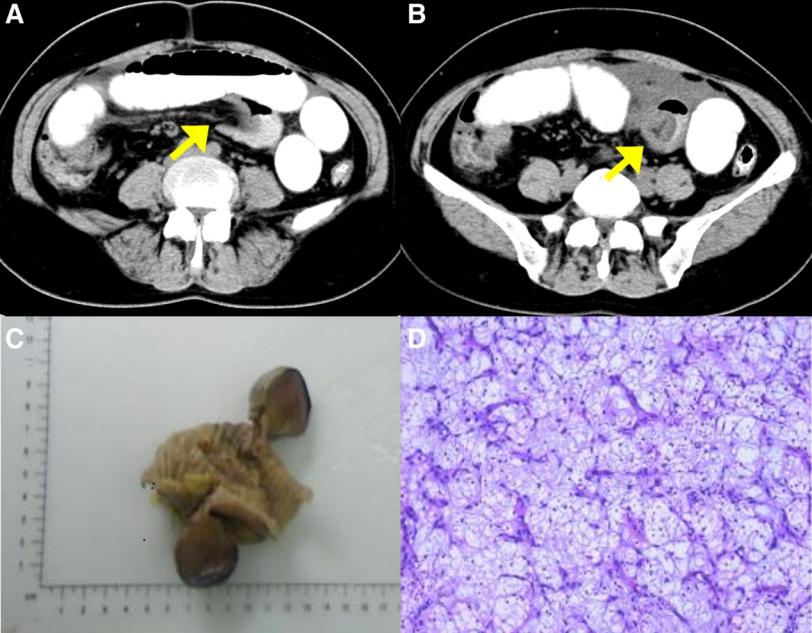

一名49岁的中国女性,有5天的间歇性下腹胀痛病史,尤其是脐周腹痛。腹部CT显示,左下腹有一段小肠插入另一段小肠,肠内积聚液体和气体(图2A和B)。患者在紧急情况下接受了剖腹探查。在剖腹手术中,距离回盲部40cm处发现了回肠肠套叠。手动复位后,发现一个3.6×3.7cm的息肉样病变浸润到浆膜层,突出并完全闭塞管腔。患者接受了持续2.5小时的部分肠切除术,估计失血量为20毫升。恢复顺利,术后8天出院,没有任何术后并发症。术后对患者进行了1.5年的密切随访,在此期间,没有报告腹部不适。后续的腹部CT扫描也没有发现复发的证据。

图2:(A-D)病例2的围手术期放射学特征和术后组织病理学特征。(A和B)腹部CT显示肠套叠的“靶征”和“杯状征”(黄色箭头)。(C) 大体标本:观察到3.6×3.7cm的息肉样病变,侵犯浆膜层。(D) 可见大量炎性细胞的背景,其中以淋巴细胞、浆细胞和嗜酸性粒细胞为主。CT=计算机断层扫描

病理检查显示,粘膜中存在3.6×3.7cm的息肉样病变,侵犯了浆膜层(图2C)。显微镜下,病变表现为糜烂、明显的间质水肿、粘液变性和血管增生。可见大量炎性细胞,以淋巴细胞、浆细胞和嗜酸性粒细胞为主(图2D)。免疫组织化学检查显示,CD34和PDGFRα呈阳性,Ki67呈局灶性阳性,CD117、DOG-1、SMA、S-100、ALK80、ER、PR和Desmin呈阴性。这些形态学和免疫组织化学结果与IFP相符。